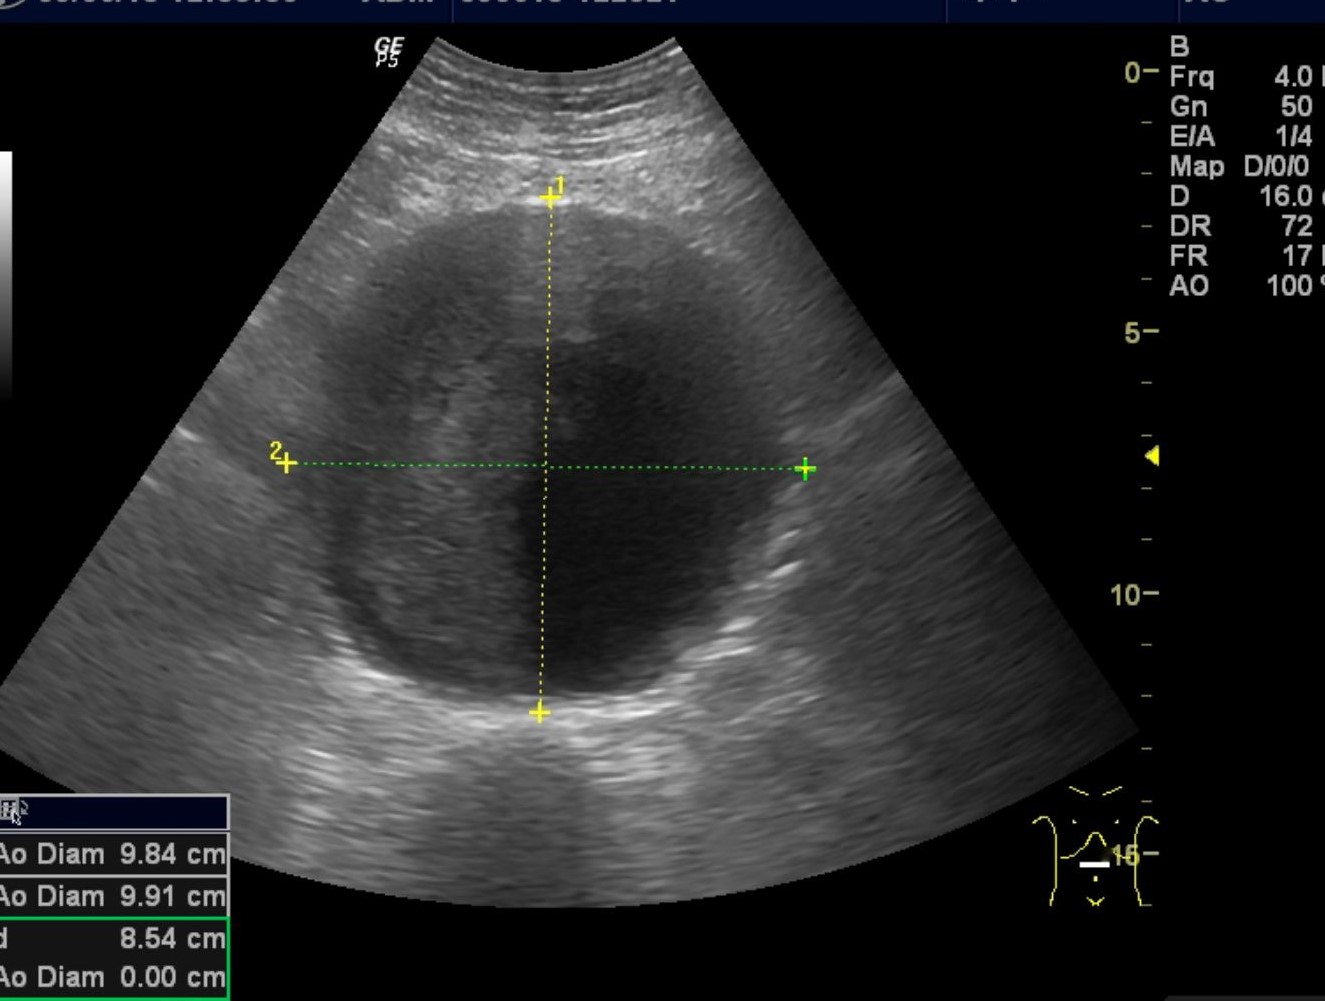

Eksempel på bruk av ultralyd i allmennpraksis. Abdominal aortaaneurisme oppdaga grunna pasientens subjektive opplevelse av pulsering i abdomen. Samtykke til undervisingsbruk frå pasient.